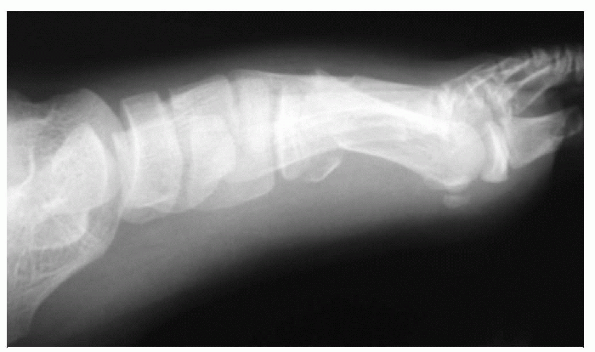

proximal end that articulates with a relatively straight ulna during

forearm rotation. Muscles that attach to the forearm and act as

potential deforming forces in fractures include, proximally, the biceps

and supinator and, more distally, the pronators teres and quadratus.

supinated proximal fragment and the position of reduction should place

the distal fragment into supination. Fracture at the midshaft should be

reduced and stabilized in neutral. Fractures of the distal third of the

radius need to be stabilized in neutral to slight pronation due to the

activity of the pronators on the proximal fragment (Fig. 12.4-1)

![]() |

|

Figure 12.4-1 Musculature of the forearm.

Figure 12.4-2 Anterior radial head dislocation with apex anterior ulna fracture.